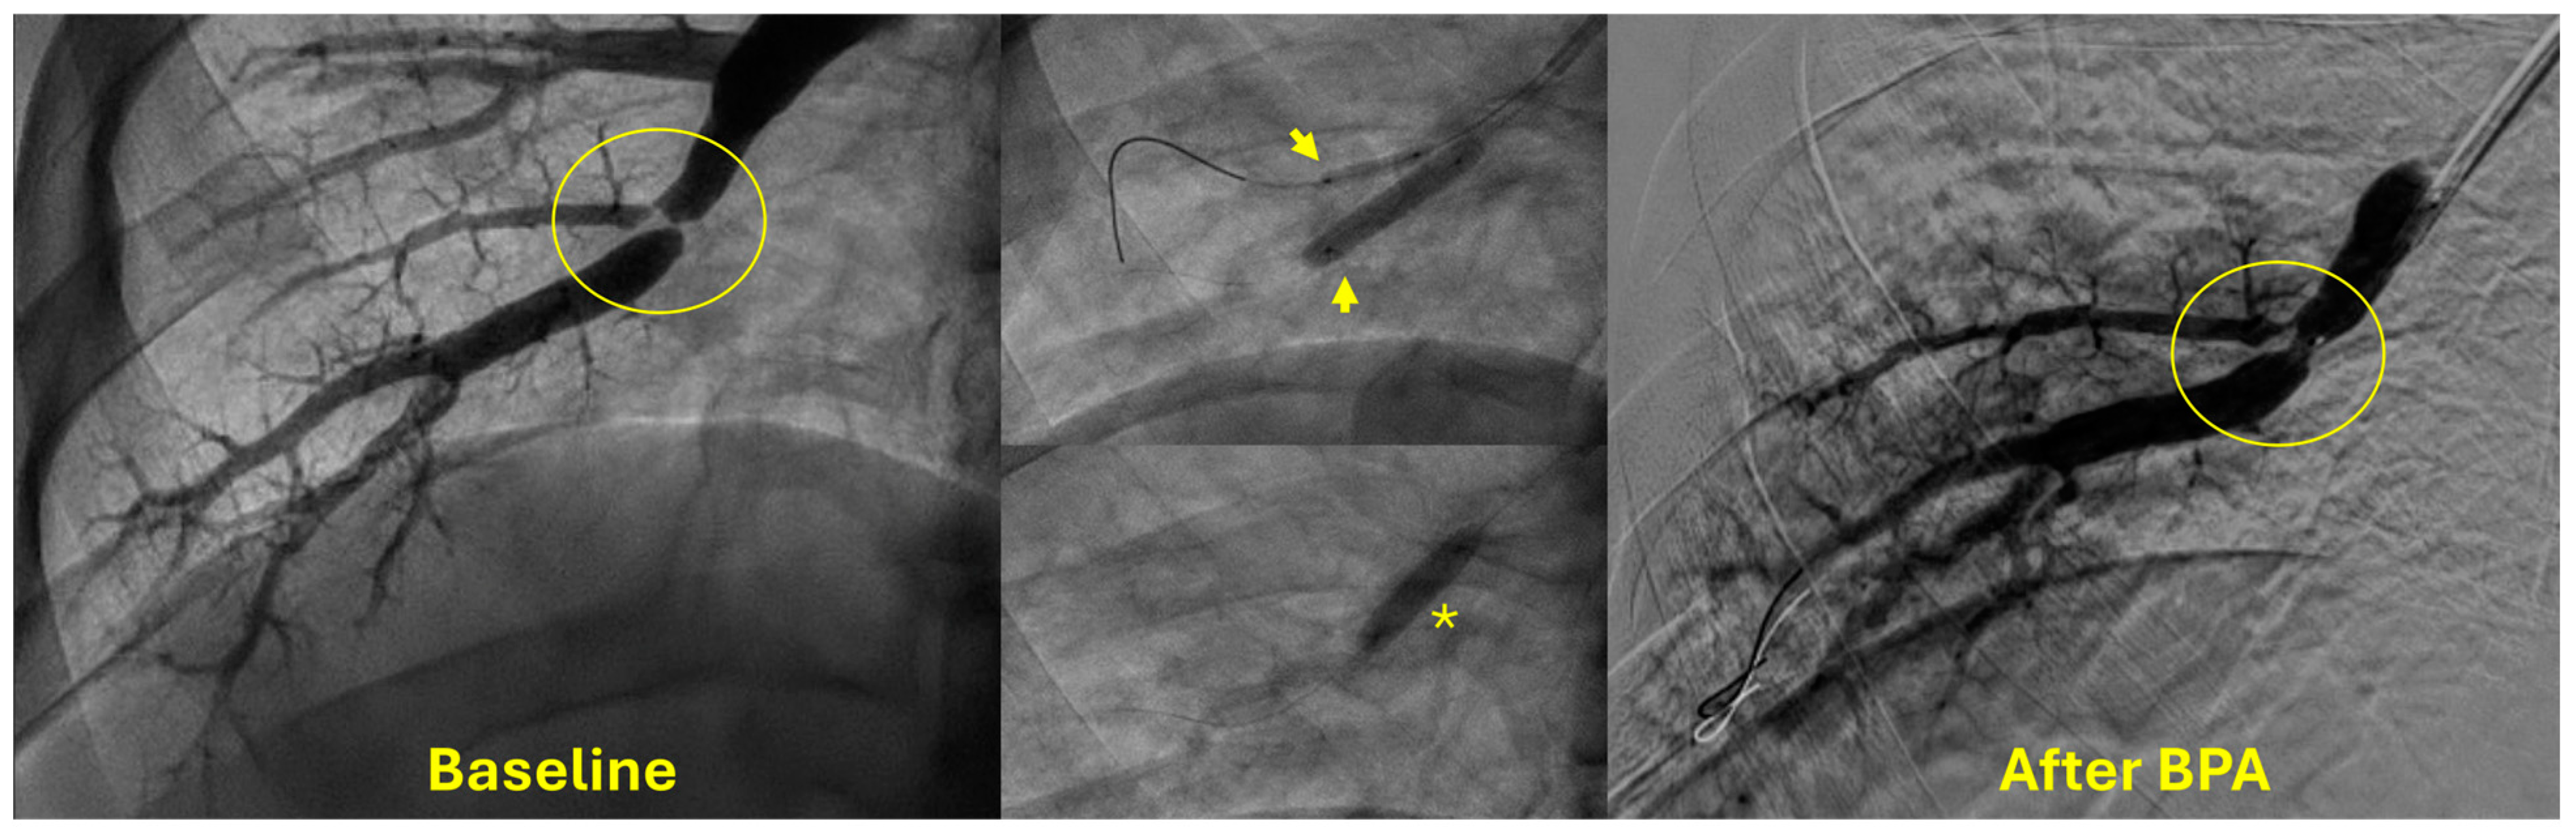

4. Indications and Patient Selection for BPA

5. Technical Considerations